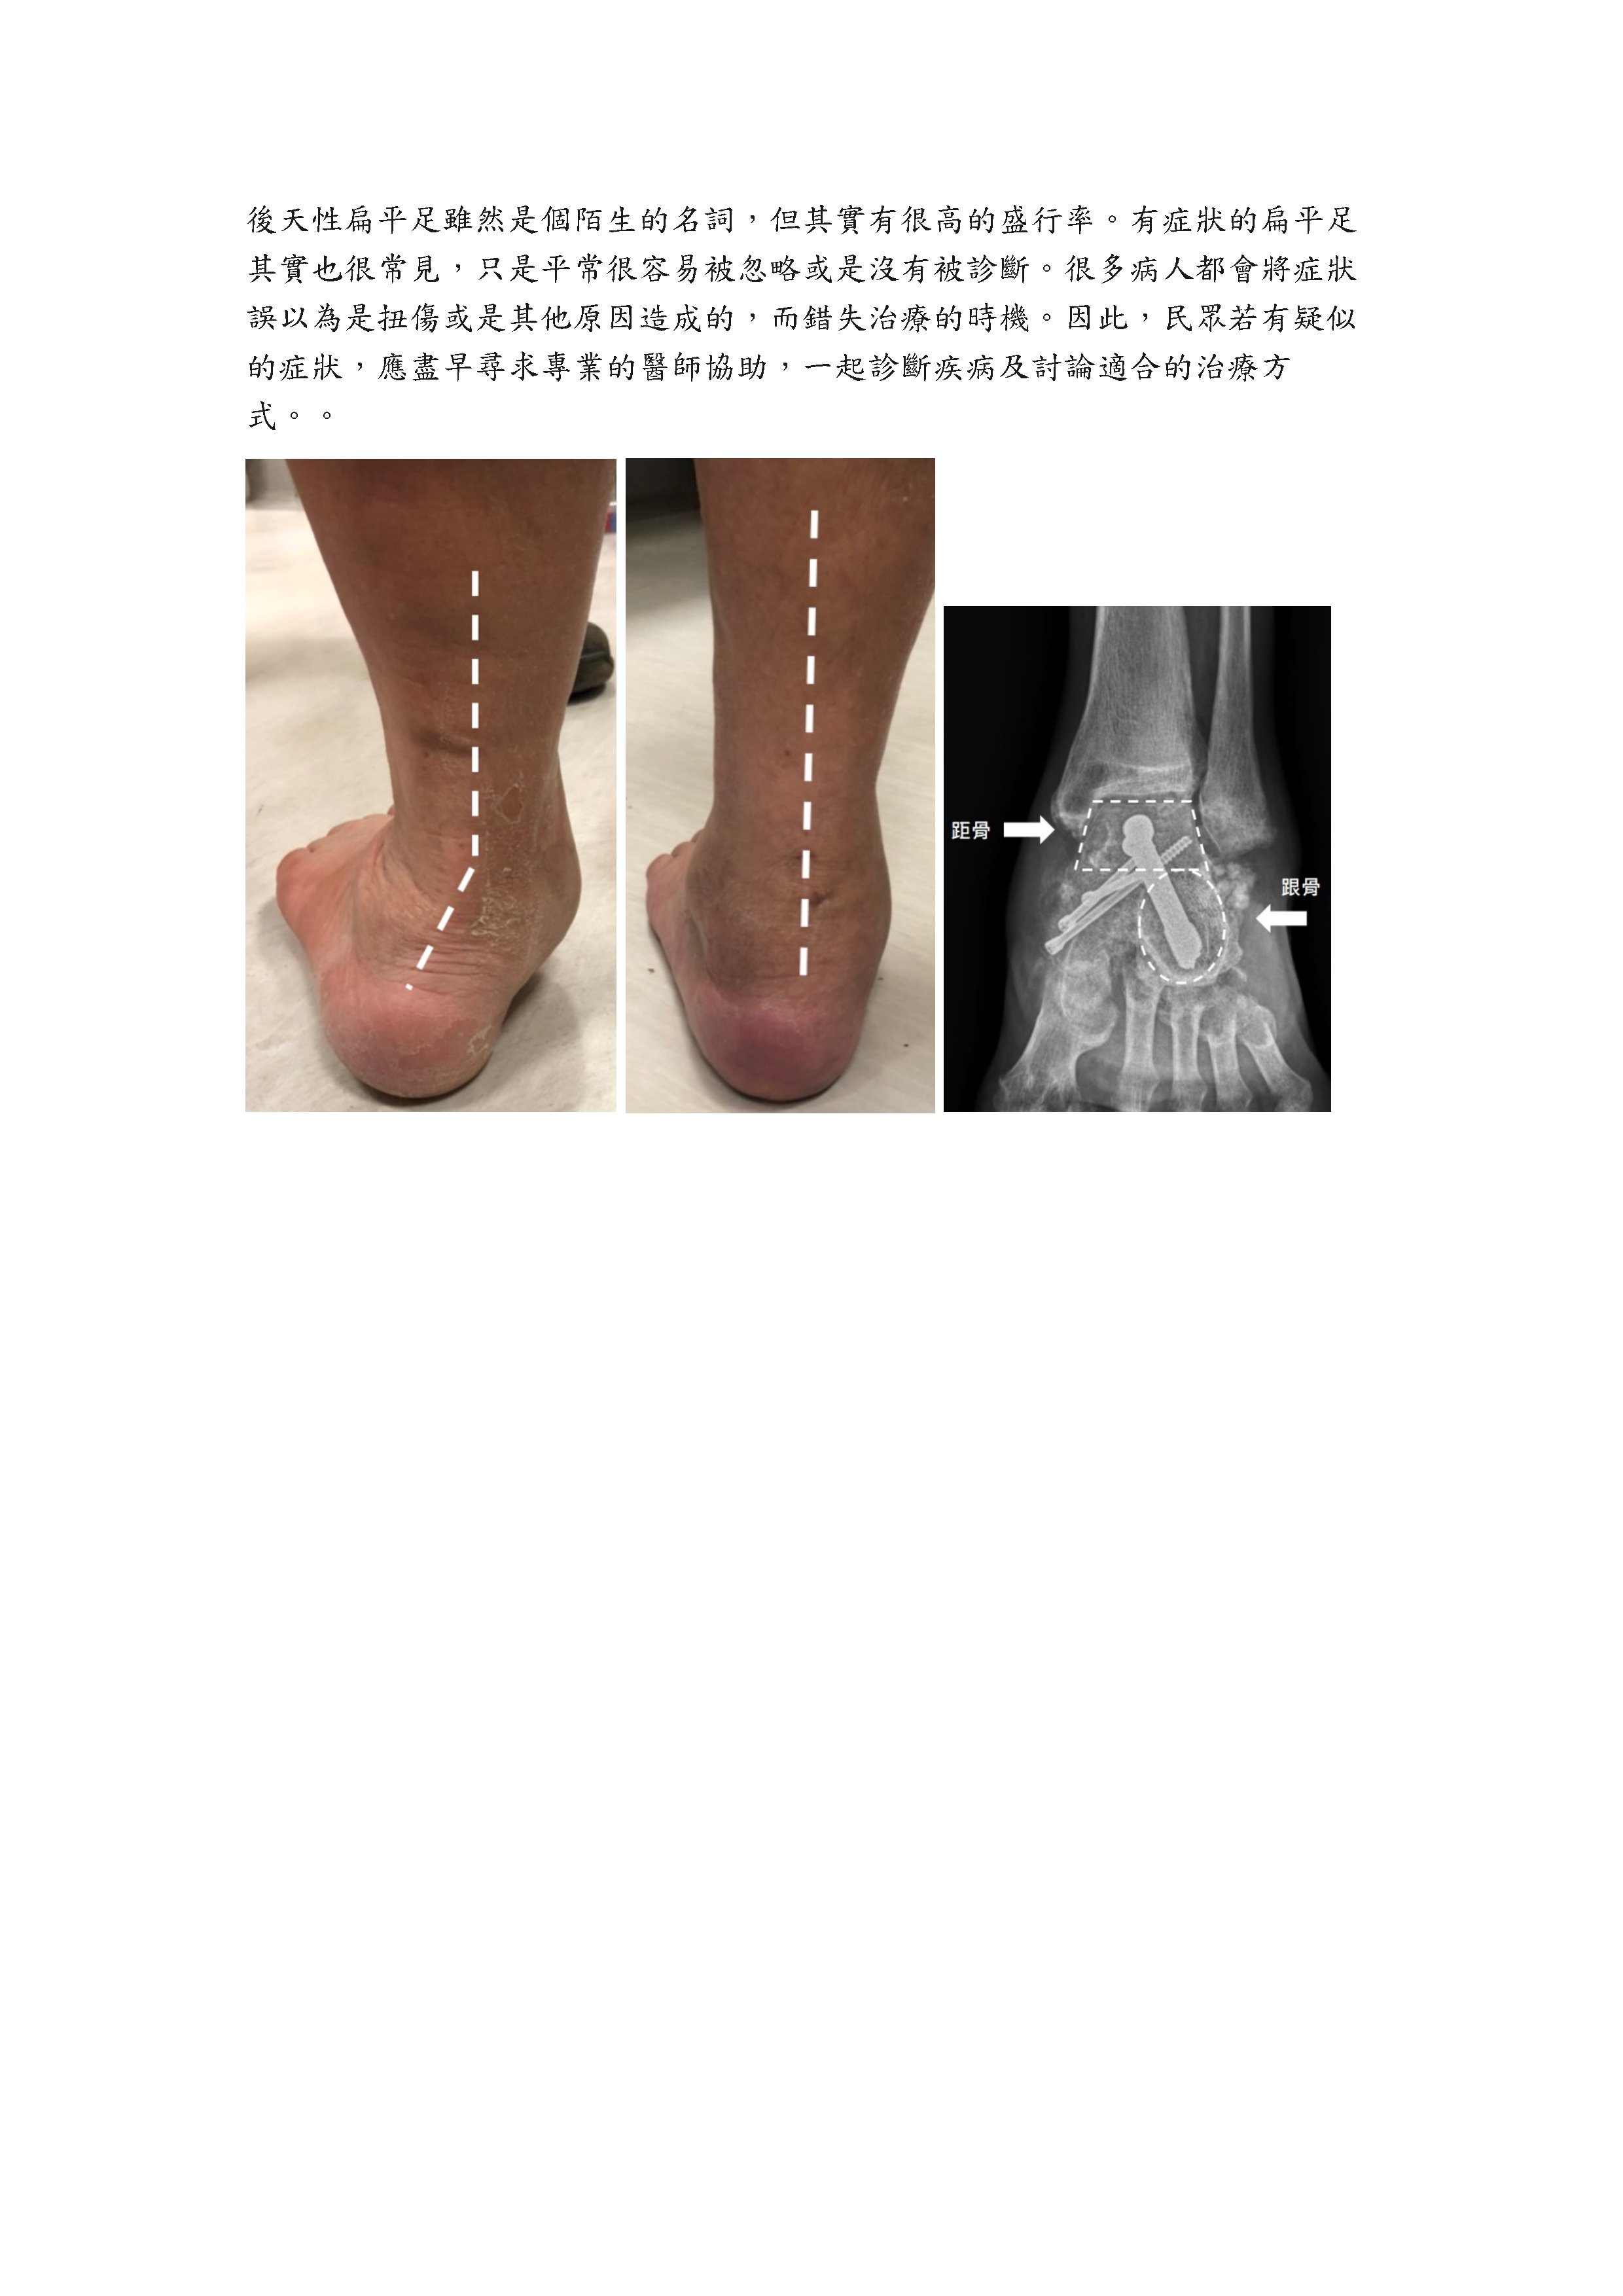

足踝外科衛教